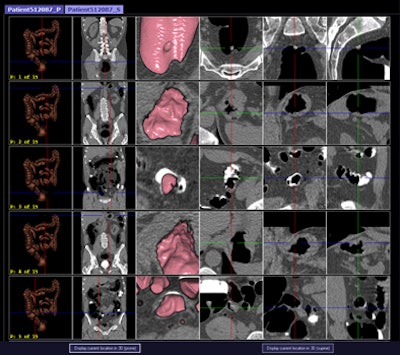

CAD first-reader gallery evaluation shown in a screening patient with a 10-mm tubular adenoma in the rectum. Above (left monitor), all 15 CAD markers in a volume are presented to the reader, line by line, as a collection of CT image galleries. They are sorted top to bottom by decreasing level of confidence, as computed by the CAD algorithm both for the prone (shown) or for the supine (not shown) position. CAD finding P:1 (first row of images) displays the polyp (crosshair) in all six gallery images. Note that the typical imaging characteristics of a polyp are already recognizable within the gallery images. The remaining CAD findings P:2-P:5 (image rows 2-5) display false-positive detections in the stomach (P:2), on the residual fluid layer (P:3), in the stomach (P:4), and in the terminal ileum. CAD findings P:6-P:15 are not shown. Below (right monitor), standard axial and optional coronal and sagittal 2D images (not shown). Optional 3D target views (not shown) of prone and supine datasets are used, first, to further evaluate potential polyp candidates or CAD findings on complex structures and, second, to perform a complete 2D review of the prone and the supine CTC datasets. The 2D axial prone and supine CT images show the polyp (crosshair) marked by CAD (marker 1) in both positions. All images courtesy of Dr. Thomas Mang.